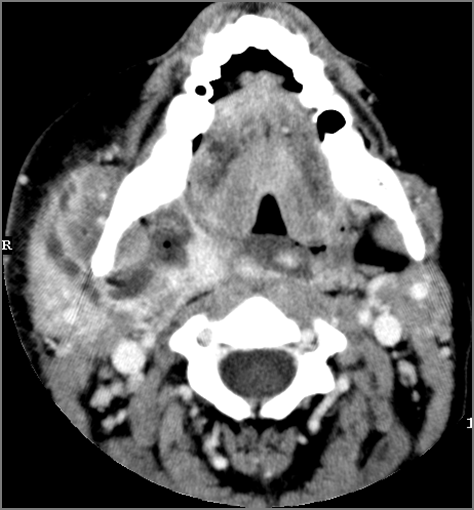

52-year old male with fever, dysphagia and possible aggressive pharyngitis or other infrahyoid neck infections involving the infra hyoid deep neck.Exam

There is general or localized soft tissue swelling of the superficial or deep neck soft tissues. |

There is edema/abscess tonsillar or otherwise or likely suppurative retropharyngeal adenitis involving the oropharynx or adjacent deep tissue spaces. |

There is edema/abscess arising from the hypopharynx, larynx, thyroid gland or trachea. |

There is edema/abscess within the adjacent deep neck, and/or retropharyngeal space. |

Severe pharyngitis with no evidence of abscess